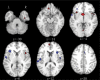

Results: Less gray matter in the high-risk group relative to controls was observed in anterior cingulate regions, left amygdala, and right insula. Lower gray matter volumes in FES compared with controls were also found in the anterior cingulate and right insula but not the amygdala. Lower gray matter volumes in the chronic group were most extensive, incorporating similar regions to those found in FES and high-risk groups but extending to superior temporal gyri, thalamus, posterior cingulate, and parahippocampal gryus. Subtraction analysis revealed less frontotemporal, striatal, and cerebellar gray matter in FES than the high-risk group; the high-risk group had less gray matter in left subcallosal gyrus, left amygdala, and left inferior frontal gyrus compared with FES. Subtraction analysis confirmed lower gray matter volumes through ventral-dorsal anterior cingulate, right insula, left amygdala and thalamus in chronic schizophrenia relative to FES.

Conclusions: Frontotemporal brain structural abnormalities are evident in nonpsychotic individuals at high risk of developing schizophrenia. The present meta-analysis indicates that these gray matter abnormalities become more extensive through first-episode and chronic illness. Thus, schizophrenia appears to be a progressive cortico-striato-thalamic loop disorder.